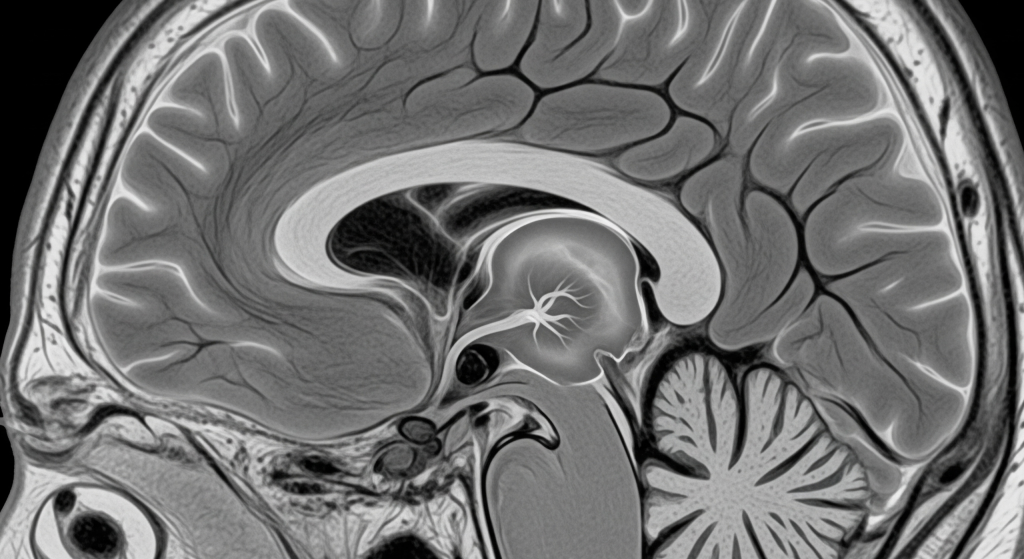

Diagnosis and The Role of MRI and MRA

Diagnosing a brain aneurysm, especially an unruptured one, is often done through advanced imaging. Magnetic Resonance Angiography (MRA) is a specialized type of MRI scan that provides detailed images of the brain’s blood vessels. This non-invasive technique uses a strong magnetic field and radio waves to create a clear picture of the arteries, allowing a neurologist to identify an aneurysm’s size, shape, and location. For an unruptured aneurysm, a MRA is a crucial tool for both diagnosis and monitoring. If a rupture is suspected, a CT Angiography (CTA) or a traditional cerebral angiography may be performed to confirm the diagnosis quickly.

How does an MRI detect a brain aneurysm?

An MRA (Magnetic Resonance Angiography) is a specialized MRI scan that focuses on blood vessels. It can clearly visualize the bulge of an aneurysm on the artery wall, providing critical information for a neurologist.